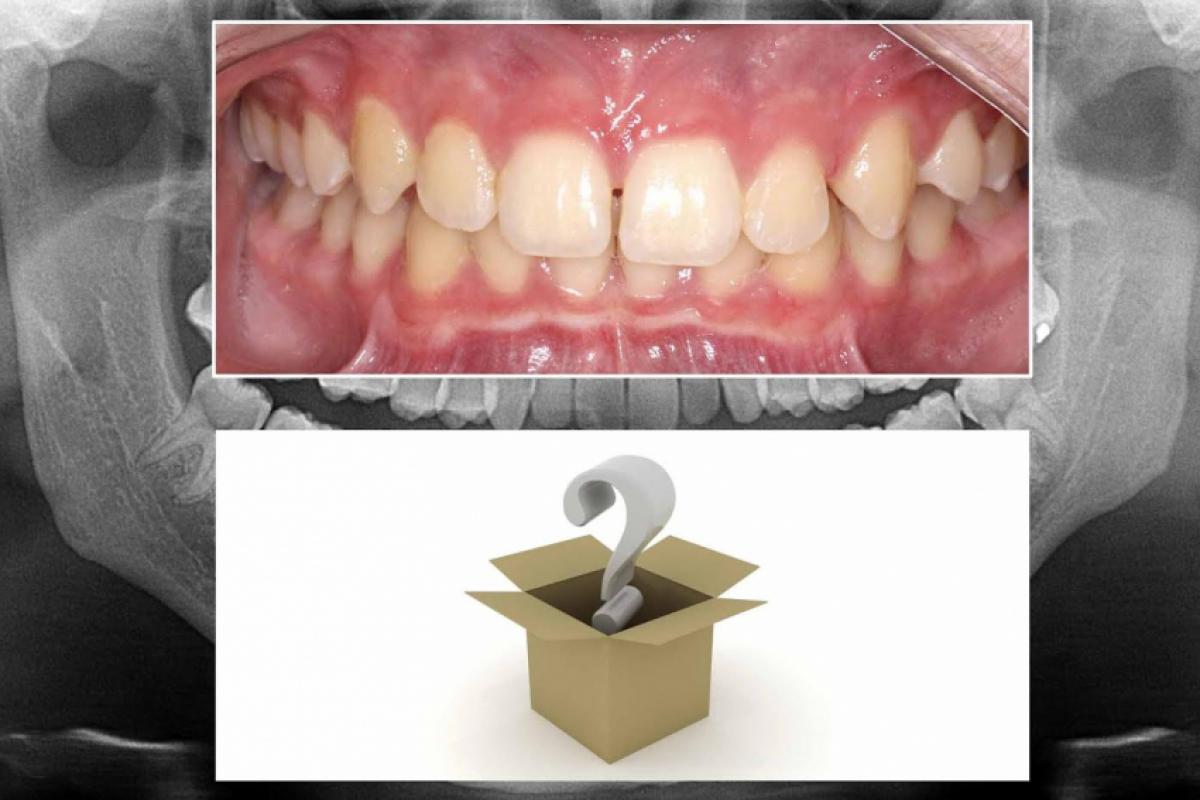

Como saber o que se tem nas raízes dentárias e ossos maxilares se não obtivermos imagens previamente para visualizá-los?

As doenças nos maxilares seriam diagnosticadas precocemente, ou até evitadas, se todos os profissionais adotassem o protocolo se obter imagens radiográficas e ou tomográficas antes de qualquer tratamento, mesmo que afetasse apenas o esmalte ou tecidos moles.

Doenças ósseas, cistos, neoplasias odontogênicas, tumores ósseos benignos e malignos, assim como dentes não irrompidos e alterações do desenvolvimento seriam diagnosticadas antes. Antigamente se tinha medo das radiações que seríamos expostos, mas hoje os aparelhos, acessórios e técnicas reduziram-nas, otimizando as imagens e não expondo o paciente aos seus efeitos negativos significantes.

Se todo tratamento odontológico fosse antecedido de imagens, teríamos muito mais saúde bucal. A maioria das doenças dos maxilares são silenciosas e se descobre depois de muito tempo. Antigamente, se fazia exodontia na cara e coragem, sem saber o que estava acontecendo com o osso e o próprio dente, mas isto foi 50 anos atrás, não se aceita mais isto, inclusive legalmente!